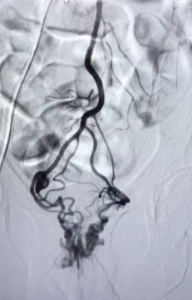

Bilan artères rectales supérieures avant embolisation

1. Le radiologue interventionnel met en place un abord artériel fémoral droit ou radial gauche et y introduit une sonde puis un microcathéter.

2. Il cathétérise l'artère mésentérique inférieure, puis les artères rectales supérieures qui sont alors occluses à l'aide de micro coïls (petits fils de platine souvent fibrés).